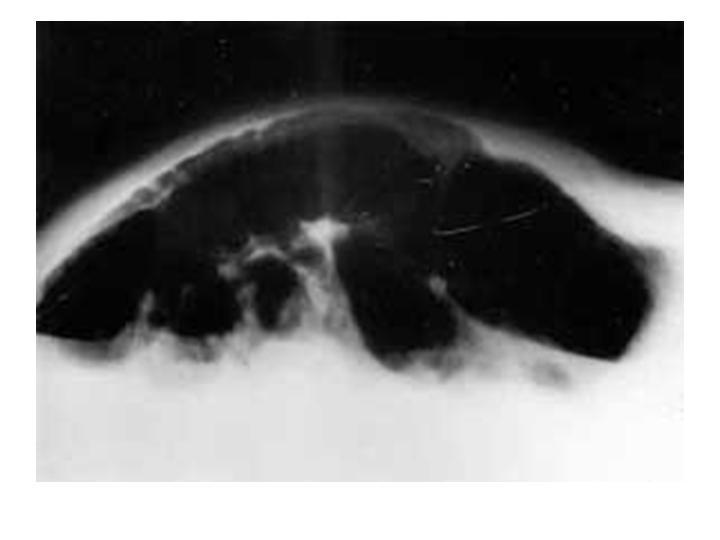

Síndrome De Ogilvie

Coloproctología

| Autor: Dra. Magdalena Bravo H.